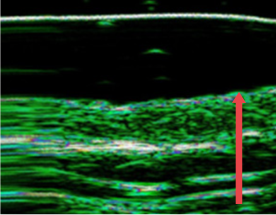

Cải thiện lớp trung bì của da bị mỏng do lão hóa, điều trị thường xuyên và kích thích bên ngoài,

trước thủ thuật

Sau 4 tháng

(độ dày tầng trung bì tăng 12%)

Sau 7 tháng

(độ dày tầng trung bì tăng 27%)